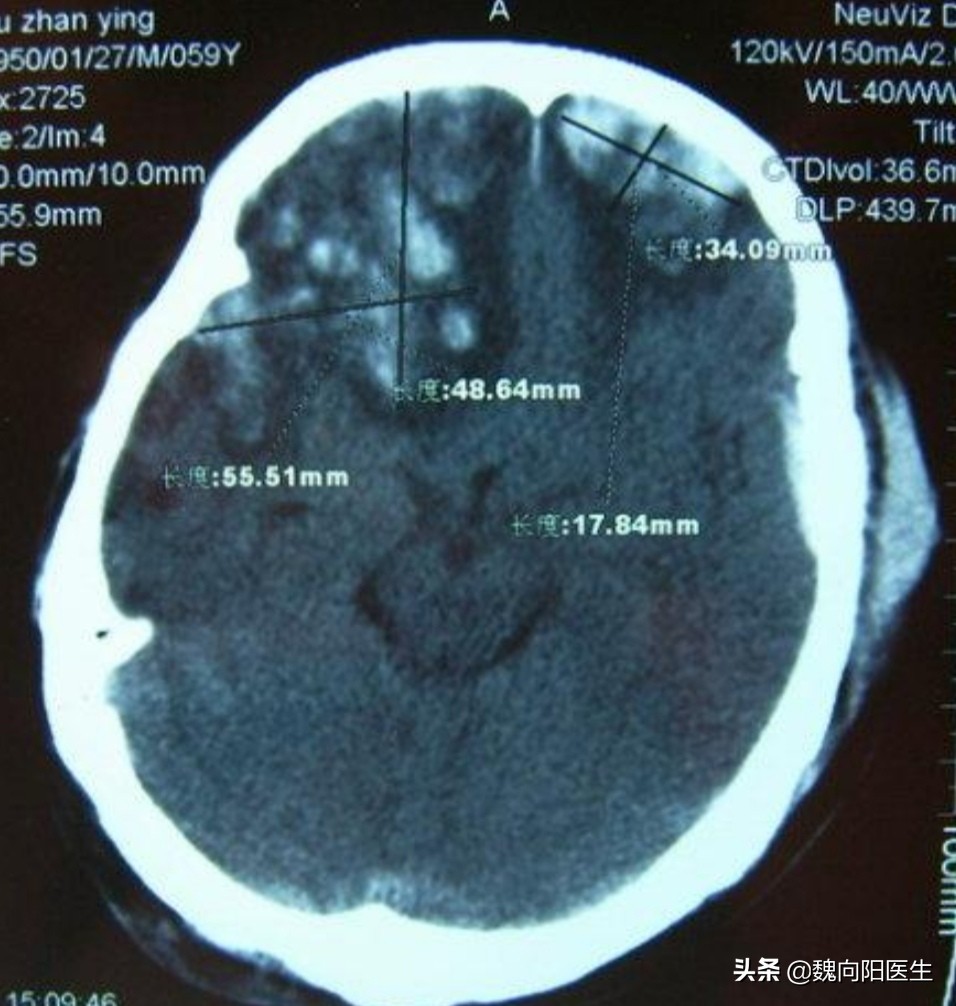

一般撞到头部后脑勺,很多脑出血是发生在前额或前颅底部位。这叫做对冲伤。

早期出现脑额颞叶挫裂伤

由于前颅底骨头表面不光滑,且神经策划众多,在后枕部受到撞击后,导致脑策划在不光滑颅骨表面滑动,从而导致脑挫裂伤、硬膜下血肿或蛛网膜下腔出血可能。